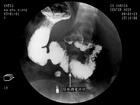

X線的特徵為:

(1)十二指腸降部擴張,或有胃擴張;

(2)造影劑在十二指腸水平部遠側脊柱中線處中斷,呈整齊的斜行切跡,通過受阻;

(3)鋇劑在十二指腸降部來回蠕動,甚至逆流入胃;

(4)鋇劑在2-4小時內不能從十二指腸內排空;

(5)病人俯臥位或左側臥位時十二指腸內鋇劑迅速通過水平部。 超聲檢查:空腹和飲水600ml後分別測量腸系膜上動脈與腹主動脈間夾角的度數(兩動脈間夾角小於 13·),十二指腸水平部在兩動脈間的前後徑(小於lcm),該處的近惻十二指腸降部內徑大於3cm和遠側 十二指腸的內徑和體位改變後的變化。 十二指腸淤滯症應與引起十二指腸梗阻其他疾病鑑別,應與十二指腸腫瘤、憩室、炎症以及十二指腸外 病變,如環狀胰腺、粘連、腫瘤壓迫等疾病相鑑別。此外,尚應與神經官能症引起的嘔吐鑑別。